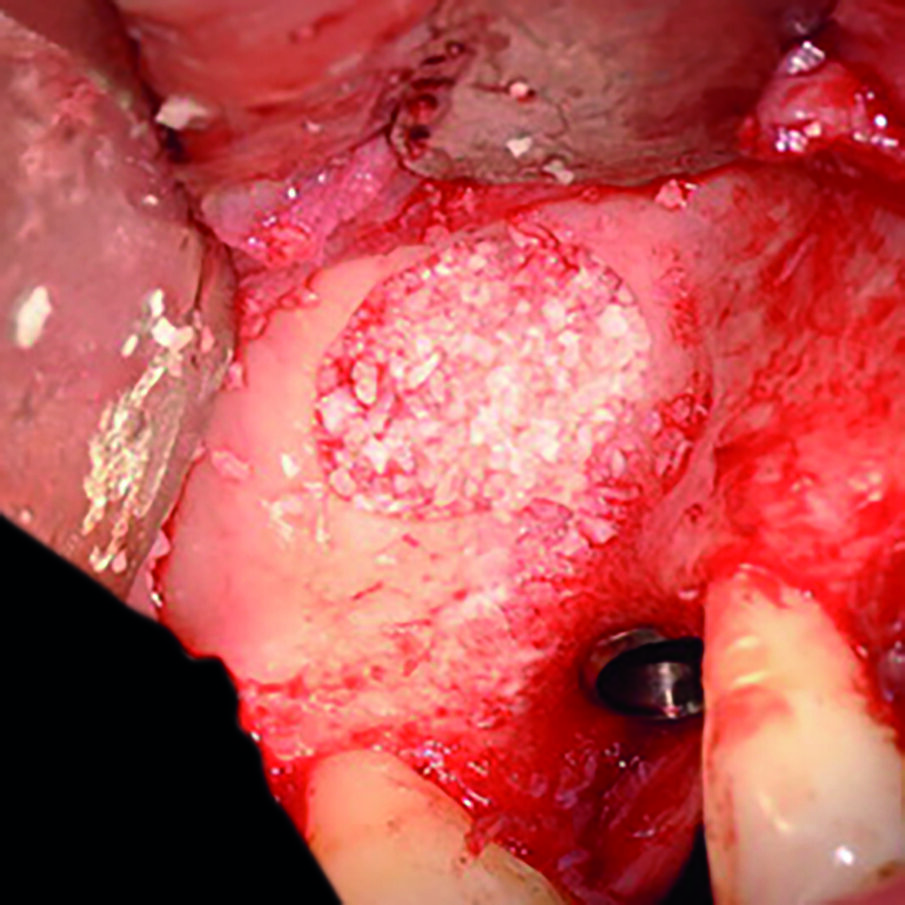

Dopo aver creato il neo alveolo si procede con il posizionamento di una membrana riassorbibile che va a ricoprire la membrana di Schneider per proteggere la stessa durante l’inserimento dell’osso sintetico. La membrana riassorbibile viene opportunamente sagomata e appoggiata sul fondo del seno mascellare facendola aderire alla membrana di Schneider (Fig. 10). Questo passaggio è utile per evitare lacerazioni della membrana da over filling.

Il passaggio successivo consiste nell’inserire osso sul fondo della camera prima di posizionare l’impianto, per evitare che quest’ultimo se inserito precocemente precluda il corretto riempimento del fondo della cavità (Fig. 11).

Apporre osso sul fondo della cavità prima di posizionare l’impianto permette, infatti, di non lasciare spazi vuoti nel seno mascellare che, se invece fossero presenti, potrebbero compromettere la durata del trattamento implanto protesico nel tempo. Nella fase successiva si procede all’inserimento dell’impianto way milano 4,5 per 10 (Fig. 12) che nei tre mm di osso residuo corticalizzato, trova una stabilità superiore ai 35 N (Fig. 13).